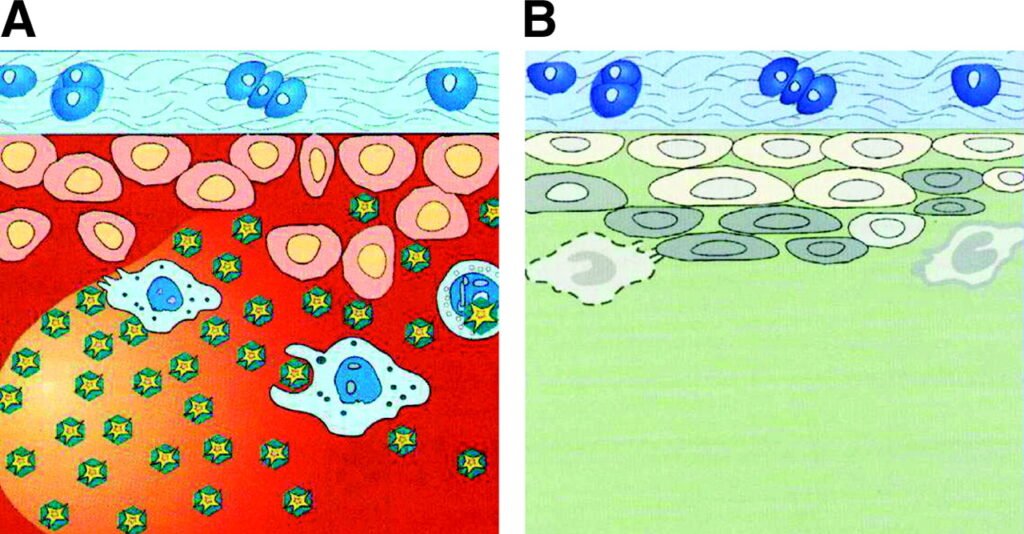

- Radioactive Iodine I-131, a beta-emitting isotope derived from stable iodine, naturally resides in the thyroid gland. This gland, located in the neck, regulates metabolism by producing hormones. When the thyroid becomes overactive, it generates excessive hormones, leading to conditions like hyperthyroidism, often caused by Graves’ disease or nodules within the gland.

- Administering a small dose of I-131 orally allows it to be absorbed into the bloodstream through the gastrointestinal tract. The thyroid gland then concentrates the radioiodine, initiating the destruction of its cells. Any surplus radioiodine is primarily eliminated through urine, swiftly exiting the body. This therapy is highly effective for managing hyperthyroidism and is often the preferred treatment.